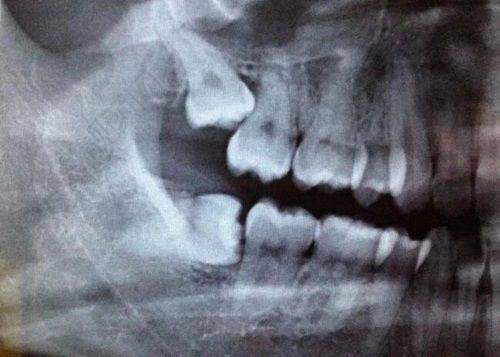

牙齿不好不仅影响吃东西,还影响咱的容貌和自信心。要是牙齿有问题,选个合适的牙冠特别重要。今天就给大家说说云阳众植博仕口腔的爱尔创全瓷牙冠,只要880元起,还有专精的张烨医生给咱保驾护航!

在云阳众植博仕口腔,爱尔创全瓷牙冠只要880元起。这价格在市场上可是相当实惠了。要知道,全瓷牙冠的价格受好多因素影响,像品牌、材料、制作工艺啥的。爱尔创是国内比较有名的牙冠品牌,质量有保护。在云阳众植博仕口腔,这个价格能拿到爱尔创全瓷牙冠,真的是性价比极高。而且医院也说了,这个价格只是个起步价,具体的还得根据每个人的口腔情况来定。要是口腔状况比较复杂,可能价格会稍微高一点,但总体来说,还是特别划算的。

爱尔创全瓷牙冠有特别多优点。首先,它的美观度特别高。它的颜色和真牙特别接近,几乎可以以假乱真。装上之后,别人根本看不出来你戴了牙冠,一点都不会影响咱的容貌。不像那种金属牙冠,在嘴里能看到明显的金属边,特别影响美观。

其次,爱尔创全瓷牙冠的生物相容性良好。它不会和口腔里的组织发生排斥反应,对牙龈也没有刺激。好多人戴了金属牙冠之后,牙龈会红肿、出血,但是爱尔创全瓷牙冠就不会有这些问题。这样就能更好地保护我们的口腔健康。

另外,爱尔创全瓷牙冠的强度也特别高。它能承受一定的咀嚼压力,正常吃东西都没问题。不用担心吃点硬的东西牙冠就坏了。而且它的耐磨性也不错,能用特别长时间,性价比极高。